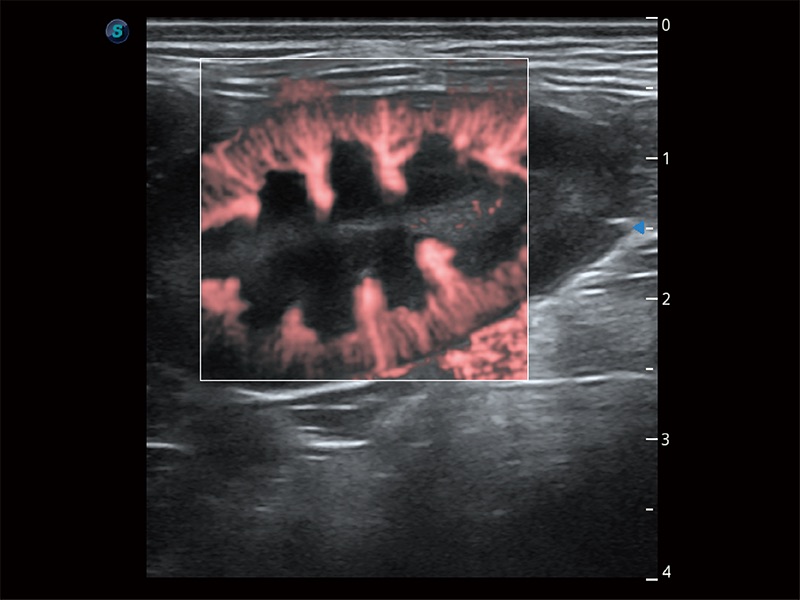

• Bright Flow 立体血流成像

在传统二维血流成像的基础上,呈现血流的立体感,具有动感的生命力之美。即便是微小的血管也能轻松应对,提高了血流的视觉敏感性。

(犬)肠道